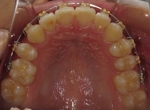

CASE5

小学1年の頃から前歯の噛み合せが逆でした。

同級生が通っていたので来ました。

(11歳/男性)↓

概要・担当医コメント:反対咬合・前歯部咀嚼障害↑

/マルチブラケット装置/非抜歯/動的治療期間24ヶ月(25回)/費用概算:60万円

治療前は虫歯のコントロールが難しい状態でしたが,矯正治療を開始してからは歯磨きを丁寧にしてくれるようになり,甘味摂取習慣の改善も行って頂いた効果があり,その後の虫歯の発生は無く現在に至っています.